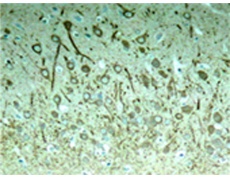

IHC positive control: |

Rat hippocampal region |

IHC Recommend dilution: |

50-100 |